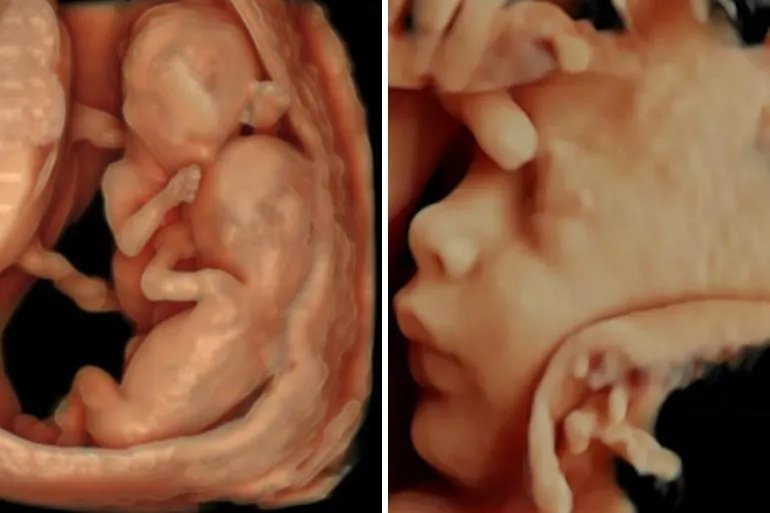

的有关信息介绍如下:概述四维彩超检查不仅满足了准妈妈的好奇心,也是监测宝宝健康最先进的方法之一。通过四维彩超可以找出畸形和胎儿真实照片,了解胎儿在宫内的发育情况。以前B超设备只能检测胎儿的生理指标。现在四维彩超对畸形儿的诊断准确率很高,可以有效减少畸形儿的出生。时间a.第一次检查,最好选择怀孕14周左右在此期间,可以在所有表面上显示胎儿头部、身体和四肢的完整图像。四维实时检查时,可以观察胎儿整体活动是否协调。但此时胎儿面部显示效果较差,内脏不清。

14周左右四维彩超图片b.复检可以在孕22周左右进行此时的胎儿比以前更大,不能在同一张图中显示胎儿的整体结构,但胎儿的局部结构和运动状态比以前更清晰。可发现严重的胎儿畸形,如无脑儿、严重脑膨出、严重开放性脊柱裂、严重胸膜壁缺损伴内脏外翻、单腔心脏、致命性软骨发育不良等。

22周左右四维彩超图片c.怀孕26周左右可以做第三次检查这个时期的胎儿皮下脂肪更多,面部表情也更丰富,胎儿各个部位也更清晰。不仅对上述畸形的诊断更加清晰,而且胎儿的面部畸形如吃手指、喝羊水、打哈欠、哭闹等都清晰可见。